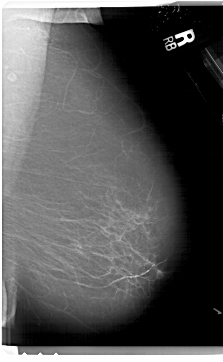

A_1627_1.LEFT_MLO

LEFT_MLO LINES 6871 PIXELS_PER_LINE 3961 BITS_PER_PIXEL 12 RESOLUTION 43.5 OVERLAY

FILE: A_1627_1.LEFT_MLO.OVERLAY

TOTAL_ABNORMALITIES 1

ABNORMALITY 1

LESION_TYPE MASS SHAPE IRREGULAR MARGINS ILL_DEFINED

ASSESSMENT 4

SUBTLETY 2

PATHOLOGY MALIGNANT

TOTAL_OUTLINES 1

BOUNDARY